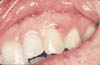

Figure 1c

Cliquez ici pour une grande image

Ill. 1c: Maintien en place du greffon par le cyanoacrylate.

Après avoir bien positionné le tissu prélevé sur la zone réceptrice, j’applique une pression avec les doigts pendant environ quatre minutes. À l’aide d’un instrument spécial, j’applique du cyanoacrylate tout autour de la jonction entre le greffon et la zone réceptrice afin d’aider à consolider la greffe (Ill. 1(c)). La couleur distincte de l’adhésif tissulaire facilite cette opération. Un applicateur adéquat permet de manipuler et de placer le matériau avec précision. On doit prendre soin de ne pas laisser le cyanoacrylate s’infiltrer entre le greffon et la zone réceptrice. On peut enlever les quantités excessives du matériau en tamponnant avec un bâtonnet ouaté. Une ou deux applications de cyanoacrylate devraient suffire pour assurer une bonne prise entre les tissus.